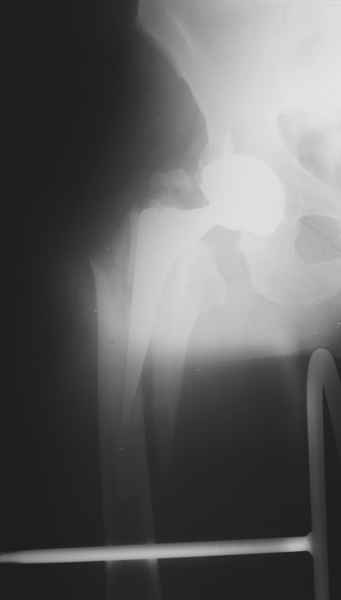

1.Остеосинтез на ножке. Мне кажется, что применительно к этому случаю малоперспективный вариант. Синтез хорош, когда можно его выполнить в малоинвазивном исполнении и достигнуть стабильности. Действительно, если ножка б/цементной фиксации после этого не будет иметь фиксации, то ревизия не будет иметь проблем. В представленном случае стабильность синтеза сомнительная, а проведение доп.иммобилизации приведет к контрактуре суставов.

2. Применение ножки дистальной фиксации, мы отдаем предпочтение ножке Вагнера с фиксацией проксимального отдела на ножке. Более травматичное вмешательство, но при стабильной фиксации ножки реабилитация идет в обычном режиме.

Хочется показать два подобных случая, П-ка З. 72 лет и п-т Г. 80 лет. Сразу принимаю замечание, что это были ножки цементной фиксации, просто под руками не было бесцементника.